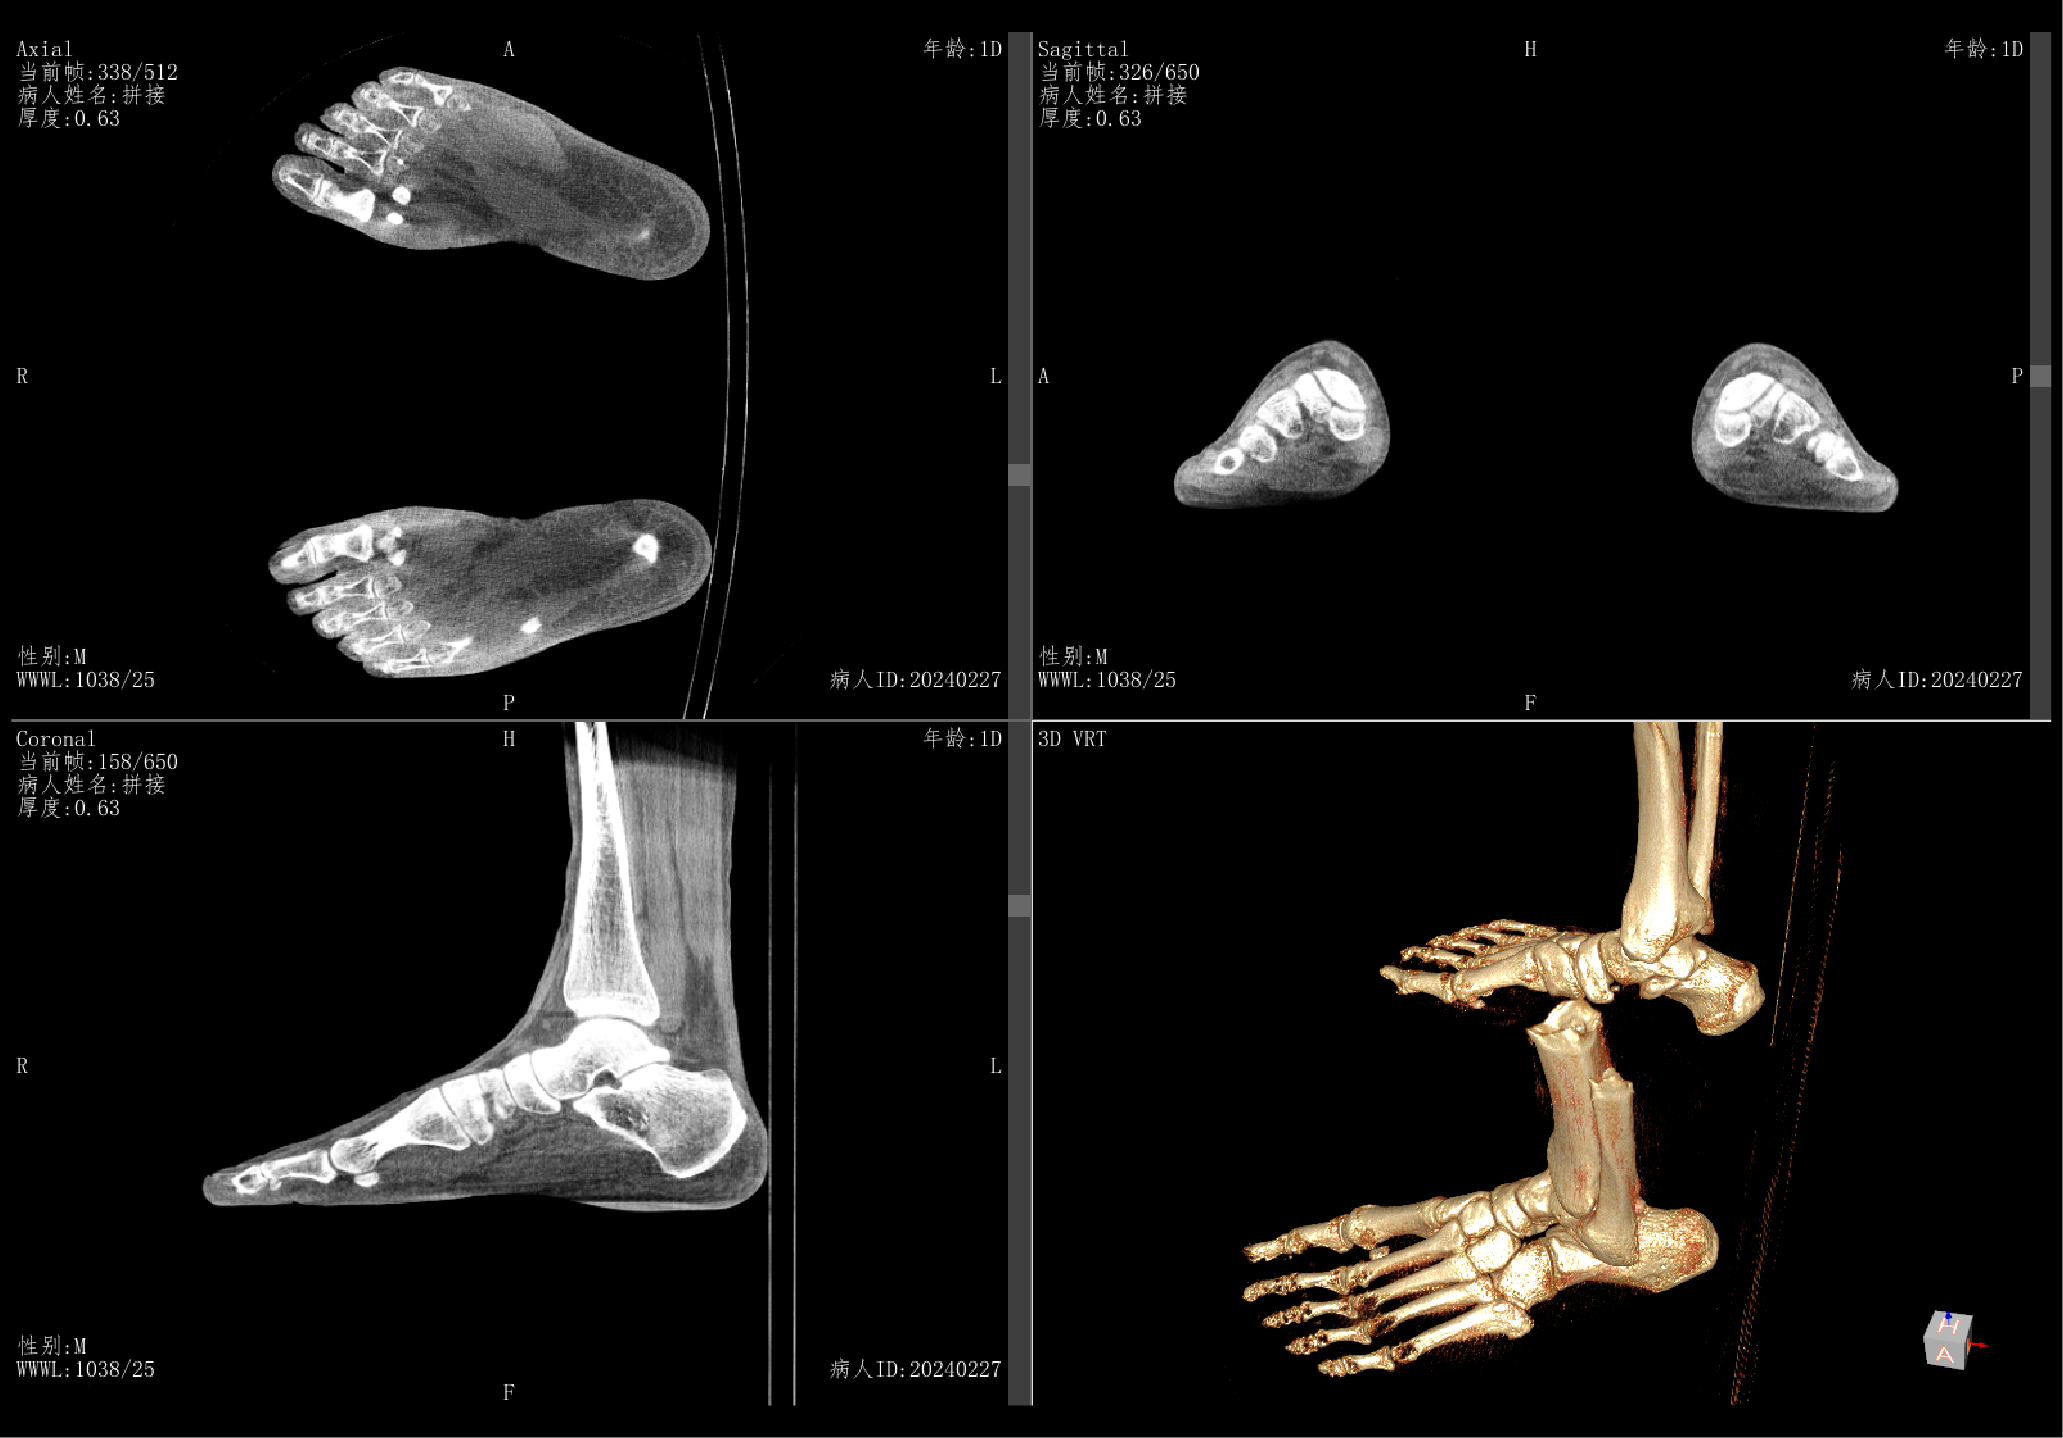

Breaking Boundaries Assisting Clinical Diagnosis with Weight-Bearing 3D Imaging

Supports bilateral ankle, knee, and joint

weight-bearing reconstruction imaging

Support MPR and 3D Reconstruction Support post-processing of Radiography, Fluoroscopy and Contrast Imaging

Provides accurate 3D imaging